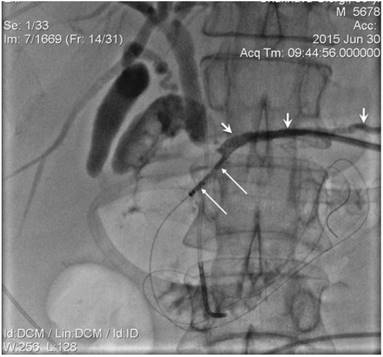

Figure 4

10 mm diameter SEMS (long arrows) positioned in CBD. Strictured segment post-dilatation was performed by balloon (short arrows).